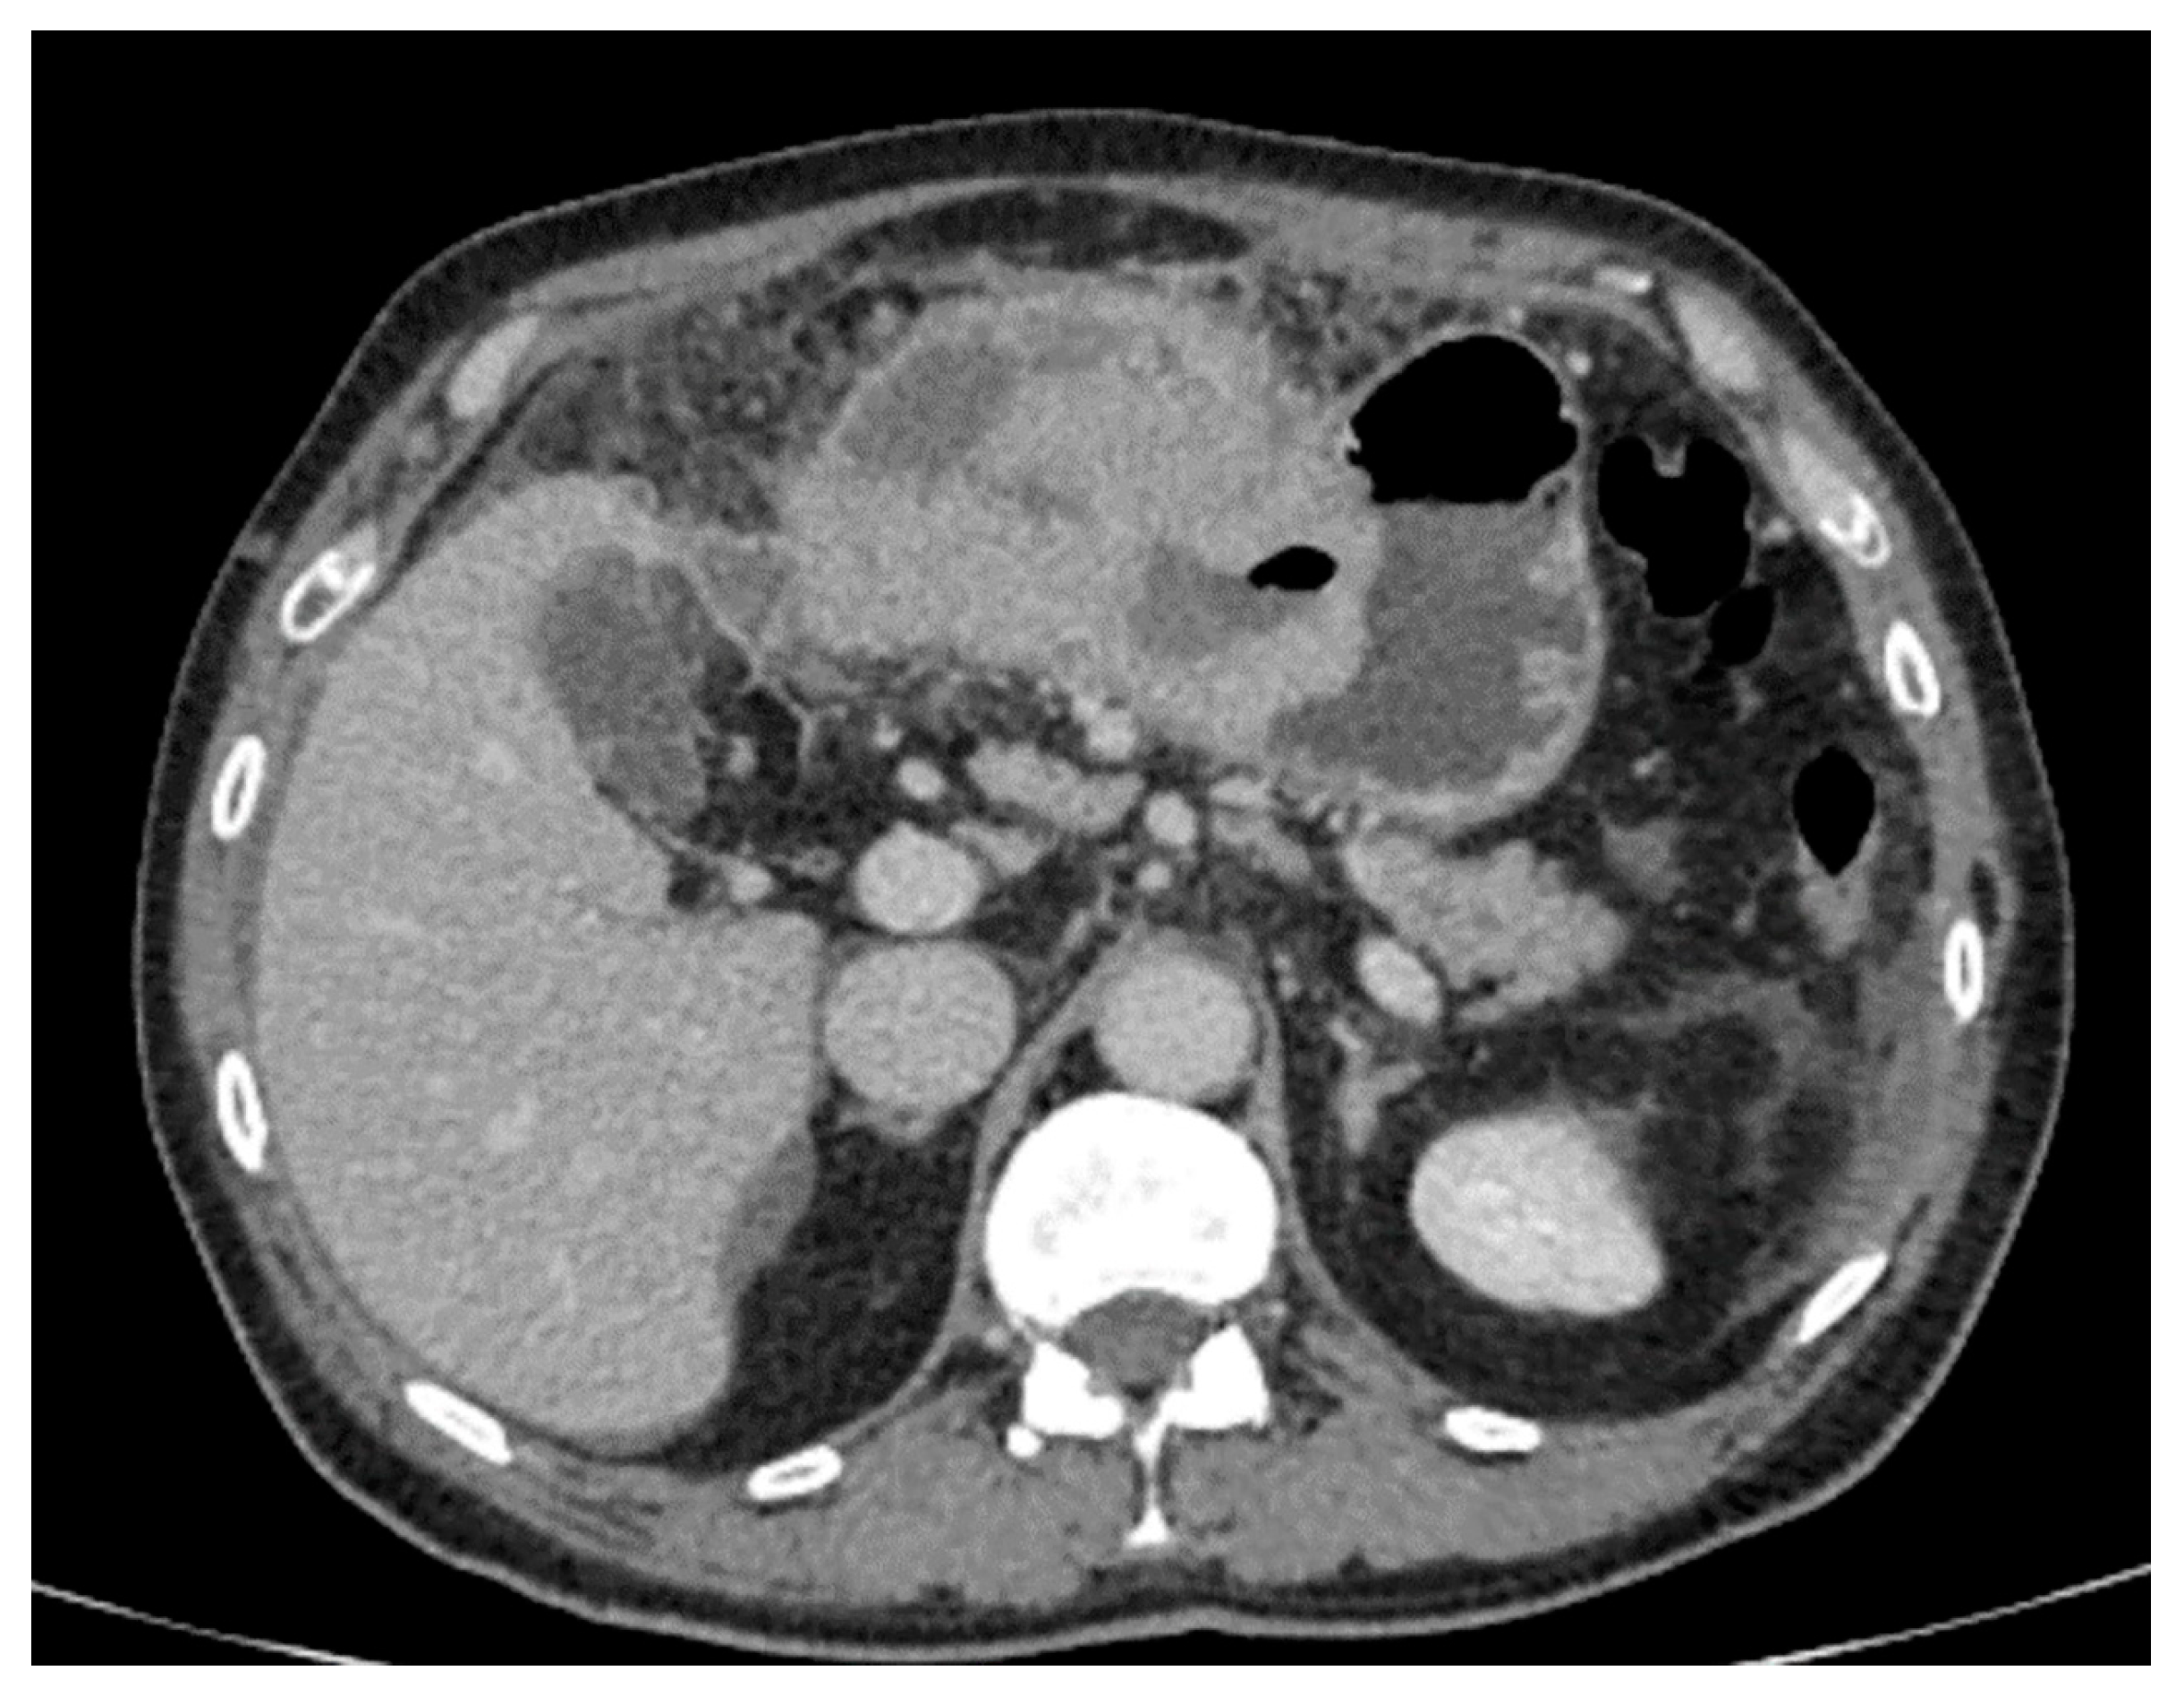

- Maximum diameter: the largest diameter of the tumor in mm (Figure 1);

- Tumor shape: regular or irregular (Figure 1);

- Growth mode: exophytic/mixed and endophytic (Figure 1);